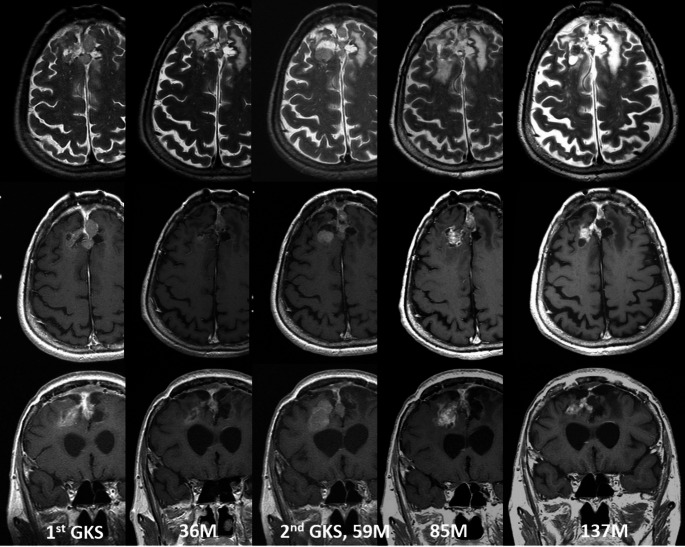

Methods: This study analyzed data extracted from the medical records of 112 patients (mean age of 57.9 years) who underwent SRS for recurrent or residual high-grade meningioma between January 2002 and December 2022. The data included clinicodemographic profiles, treatment parameters, and imaging phenotypes. The average follow-up duration was 41.7 months (range 12-160.7 months).

Results: There was slight preponderance of females in the cohort (65:47). All patients had undergone craniotomy and histopathologic confirmation of atypical or anaplastic meningioma. Gross tumor resection was achieved in 35 cases. Atypical meningioma accounted for the vast majority of cases (105; 93.8%) with only 7 cases of anaplastic meningioma (6.2%). At a median follow-up of 41.7 months after SRS, tumor control was achieved in 29.5% of cases. Kaplan-Meier analysis indicated overall actuarial progression free survival rates of 79.5%, 43.8% and 30.4% at 1, 3 and 5 years after radiosurgery, respectively. In cases involving repeated SRS, these rates were 97.6%, 69% and 45.2%, respectively. Male sex, older age, anaplastic phenotype, subtotal resection, and larger tumor volume were significantly predictive of tumor growth after treatment. Adverse radiation effects were observed in 33.8% of patients who underwent repeated SRS. Most of those patients were asymptomatic and only five patients required a temporary course of steroid therapy.

Conclusions: Our data suggest that SRS is a relatively safe and effective treatment option for recurrent or residual high-grade meningioma, with an acceptable complication profile, even when performed repeatedly. Anaplastic tumor phenotype, subtotal resection, and larger tumor volume were factors associated with tumor growth, warranting close clinical surveillance after radiosurgery.